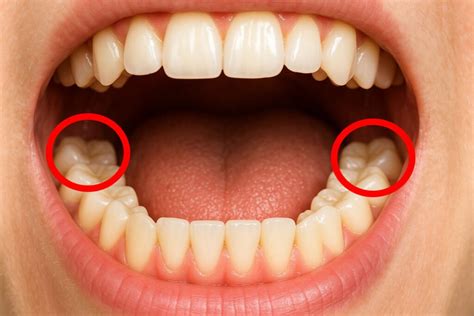

Las muelas del juicio son los terceros molares que suelen erupcionar en la edad adulta temprana (entre los 17 y 25 años). La mayoría de las personas tienen cuatro muelas del juicio, dos en la parte superior y dos en la parte inferior de la boca. Estas muelas son las últimas en aparecer y, a menudo, no tienen suficiente espacio para desarrollarse correctamente.

Las muelas del juicio pueden estar incluidas, es decir, totalmente cubiertas por la encía, lo que puede generar infecciones, quistes o daño en las raíces de los molares vecinos. En otros casos, las muelas están parcialmente erupcionadas, lo que suele provocar episodios recurrentes de infecciones y problemas periodontales debido a la acumulación de bacterias.

Tanto si están incluidas como si están parcialmente erupcionadas, pueden generar dolor y procesos infecciosos. Cuando estas muelas presentan caries, salvo en situaciones concretas, no se suelen realizar empastes y se prescribe su extracción.